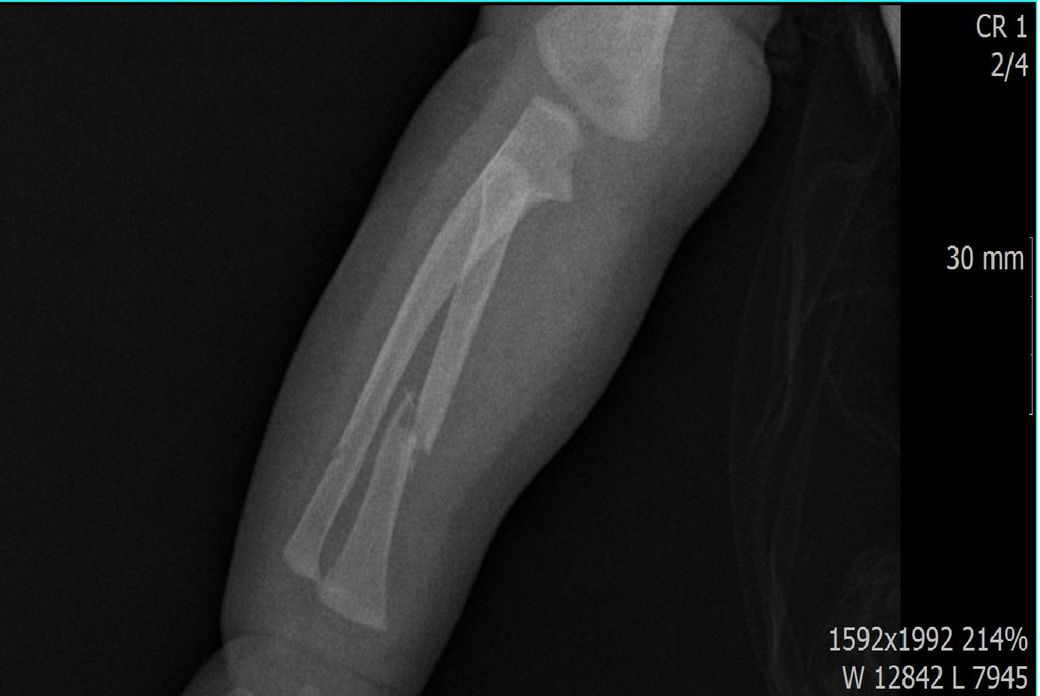

다름이 아니라, 첨부드린 엑스레이(X-ray) 사진처럼 골절 사실을 알게 되고 골절 발생 시점 대략적으로나마 추정시기를 파악하려고 문의 드리게 되었습니다

1) 3월 30일 촬영한 X-ray만으로 정확한 골절 시기를 100% 특정하는 데에는 한계가 있다는 점 충분히 인지하고 있기에 촬영날짜 기준으로 대략적으로 어느정도 시점에서 발생되었을 것으로 추측(ex 당일, 7~10일전, 7~14일 전, 10일 ~ 20일전, 14일 ~ 30일전 등등등)되는지 이해하고 싶습니다.

• 1번 째 사진

골절의 상태를 보고 골절선이 선명하고 부위에 가골이 형성되지않았다면 보통 일주일 이내로 봅니다.

골절선이 보이지만 주변 부위에 가골이 조금씩 있다면 2주 이내.

골절선이 잘안보이고 가골이 보인다면 한달 이내로 판단 할 수 있습니다.